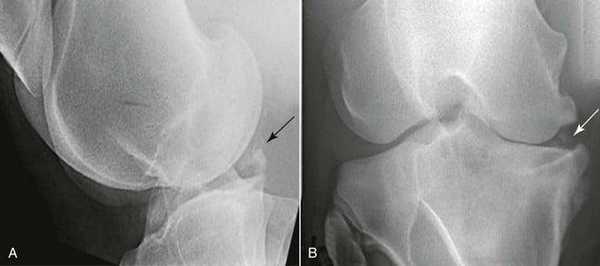

4. Стандартное рентгенологическое обследование позволяет оценить высоту суставной щели коленного сустава, выявить остеохондральные повреждения, внутрисуставные переломы, хондрокальциноз и другие патологические изменения

5. Полноразмерные рентгенограммы нижних конечностей в положении стоя выполняются для оценки оси конечностей и диагностики деформаций

• Неполные разрывы в области верхней или нижней поверхности мениска (рис. 6 и 7)